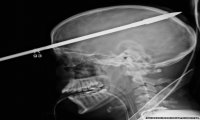

Yasser Lopez, un sedicenne americano, era andato a pesca con degli amici.

Mentre stava nuotando, ad un amico è partito accidentalmente un colpo dal fucile subacqueo. Il dardo che ne è uscito è cosi rimasto incastrato nel cranio di Yasser.

Subito portato all'ospedale è stato poi sottoposto a un'operazione durata tre ore e mezza.

L'aspetto miracoloso della vicenda è che il dardo è stato estratto senza recare nessun danno al povero Yasser, se non una amnesia riguardo all'incidente.

Secondo i medici il ragazzo è stato fortunato perché il dardo ha colpito la parte destra del cervello, evitando i centri del linguaggi e di altre funzioni importanti.